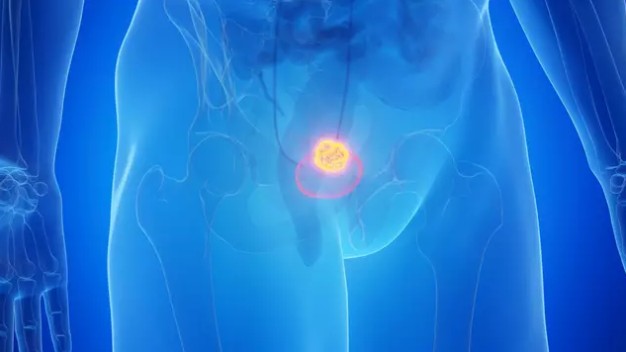

Bladder cancer survivors have spoken out on the ‘most common’ symptom they all experienced before eventually receiving their diagnosis.

According to Cancer Research, there are around 10,500 new bladder cancer cases in the UK every year – a figure which works out to be 29 every single day.

It’s also the 11th most common cancer in the UK, accounting for three percent of all new cancer cases and, for women, it’s the 17th most common cancer, whilst for men it’s the 7th.

Now, while a person’s risk of developing cancer depends on many factors – including age, genetics, and exposure to risk factors (including some potentially avoidable lifestyle factors) – as many as 49 percent of bladder cancer cases in the UK are preventable.

The most common symptom of bladder cancer

The NHS outlines that the main symptom of bladder cancer is blood in your urine – something which survivors have spoken out about to warn others to take such a symptom seriously should they experience it themselves too.

Other symptoms of bladder cancer

While blood in your urine is the ‘most common’ symptom of bladder cancer, it’s important to note that other symptoms include:

– Pain, burning, stinging or itching when you pee

– Getting lots of urinary tract infections

– Needing to pee more often

– Needing to pee very suddenly

– Losing your appetite and losing weight without trying to

– Pain in your back and lower tummy

– Aching, pain or tenderness in your bones

Feeling very tired for no reason and feeling generally unwell